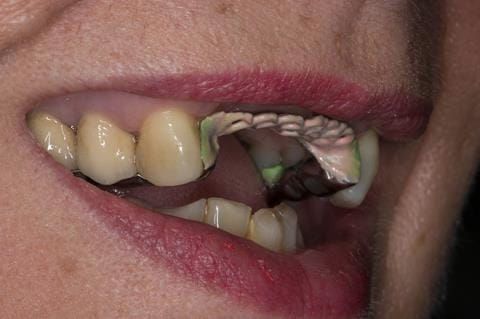

- UR2 peri-radicular periodontitis with a peri-radicular area on the root apex. Retrograde amalgam filling from a previous apicectomy. No visible root canal or root canal filling. Large circumferential marginal gap between the crown and tooth. Large post and core present. Very little tooth structure remaining resulting in a fragile tooth with increased potential for fracture.

- UR1 peri-radicular periodontitis with a small peri-radicular area on the root apex with wide blunderbuss apex. Radio-opaque root canal filling present approximately 3 mm short of the radiographic apex. Large circumferential marginal gap between the crown and tooth. Large post and core present. Very little tooth structure remaining resulting in a fragile tooth with increased potential for fracture.

- UL1 peri-radicular periodontitis with a peri-radicular area on the root apex. Retrograde amalgam filling from a previous apicectomy. Visible root canal space with no sign of root canal filling. Large circumferential marginal gap between the crown and tooth. Large post and core present. Very little tooth structure remaining resulting in a fragile tooth with increased potential for fracture.

- UL2 peri-radicular periodontitis with a peri-radicular area on the root apex. No visible root canal or root canal filling. Large circumferential marginal gap between the crown and tooth. Large post and core present. Very little tooth structure remaining resulting in a fragile tooth with increased potential for fracture.

- High smile line showing gum above gingival zeniths of upper front teeth when smiling. Aesthetic failure of the upper four incisors with inflammation of the gingivae and mis-match of the gingival zenith levels.